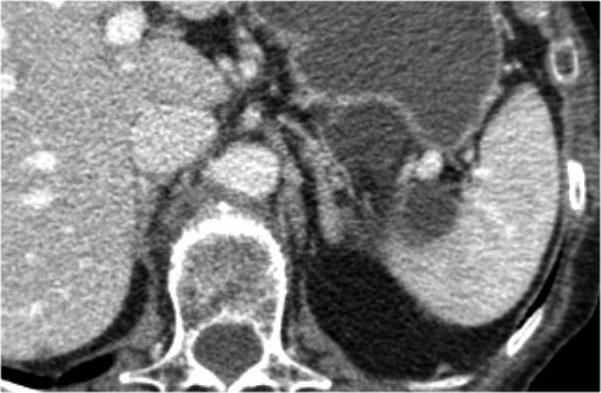

Đây là một ví dụ khác về u nang tuyến thanh dịch.

Lưu ý ngấm thuốc ở trung tâm.

Đôi khi việc phân biệt với u thần kinh nội tiết dạng nang tăng sinh mạch có thể khó khăn, nhưng trong trường hợp này vôi hóa trung tâm là dấu hiệu gợi ý hữu ích.

Cuộn qua các hình ảnh.

Ở đuôi tụy có tổn thương dạng nang với sẹo trung tâm kèm vôi hóa (mũi tên).

Mặc dù một số nang có kích thước lớn hơn 2 cm, hình ảnh này vẫn điển hình cho u nang tuyến thanh dịch, do có sẹo trung tâm, hình ảnh đa thùy và bờ viền thùy múi.

Bệnh nhân này có các triệu chứng đau bụng được quy cho khối u, khối u đã được phẫu thuật cắt bỏ và kết quả giải phẫu bệnh xác nhận là u nang tuyến thanh dịch.

Đây là bệnh phẩm sau phẫu thuật cắt bỏ.

Khối u dính vào lách, do đó lách cũng phải được cắt bỏ cùng.